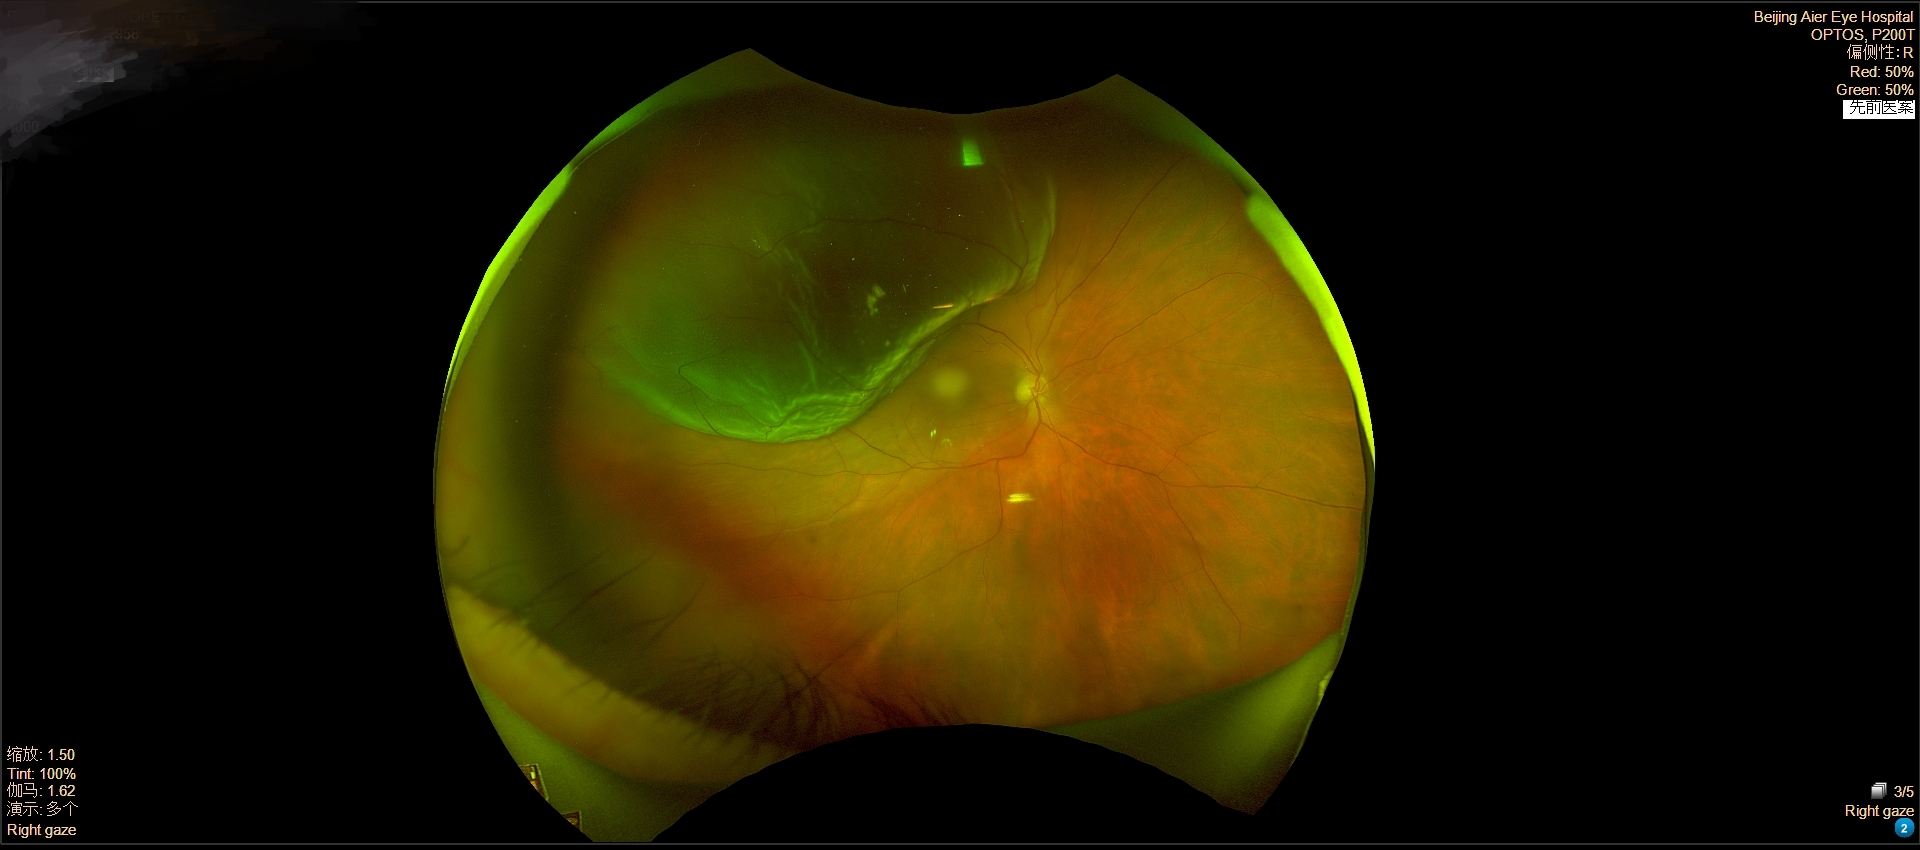

(患者术前术后眼底影像对比。)

然而,进一步检查发现,情况远比预想的复杂。患者不仅视网膜脱离范围广泛、已波及黄斑区,他还患有一种罕见的血液系统疾病——巨球蛋白血症(Walerstron)。这种疾病会让血液变得异常黏稠,同时可能伴有凝血功能异常,意味着手术和麻醉的风险大大增加:术中可能出现出血、血栓,甚至循环紊乱。

手术中,王志军教授先尝试常规的外路探查,但由于裂孔位置极为隐匿,始终找不到明确裂孔。凭借丰富的临床经验,王志军教授果断改为更为精细的内路手术方案——25G微创玻璃体切割术。这种灵活的术中决策,避免了反复无效探查,直接切除了混浊、牵引视网膜的玻璃体,最终在11点位近锯齿缘处发现了一个由玻璃体纤维牵拉形成的局部细小裂孔。王志军教授随即用激光将其封闭,并填充医用硅油,使脱离的视网膜顺利复位。整个手术在麻醉团队的严密监护下平稳完成,术中无活动性出血,患者生命体征稳定。

术后第一天,患者的右眼眼前遮挡感明显减轻,视力从术前仅能感知“手动”恢复到了0.04。